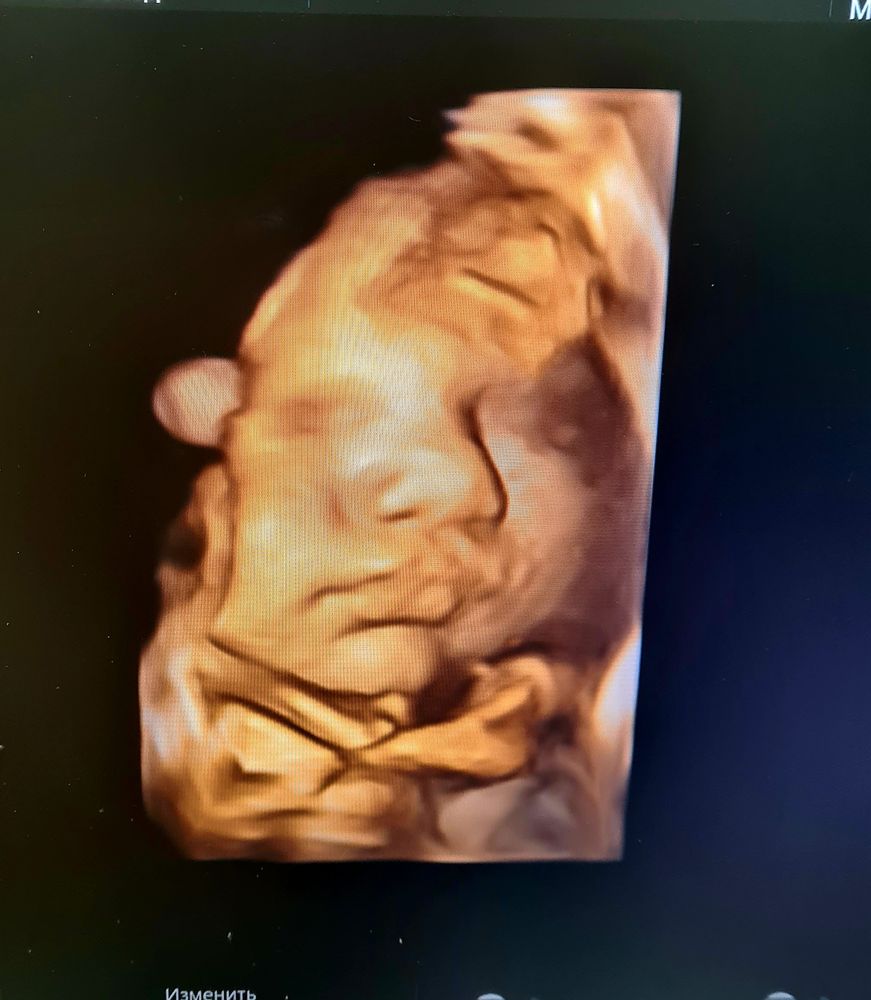

Наши будни, наши неделькиОсталось 11 дней до пдр. Предыдущая неделя тянулась медленной полосой и постоянными трениками. С разной периодичностью, но с тянущими и ноющими болями. При осмотре вердикт таков что голова низко, зев на 2 пальца, но шейка длинная....нет вернее не так-длинннннннаааааааяяяя..... вообщем 4 роды путь один). Живот не большой, но места даме мало) сегодня на узи намеряли 3500 гр, и как все те беременности удивились где же там все помещается. Морально уже настроила себя быть бойцом и все таки доходить до пдр и молить о стимуляции. Т.к. настрой дамы не выходить в этот мир, который по видимому ей и так понятен) все время она хмурила брови и дула губы.